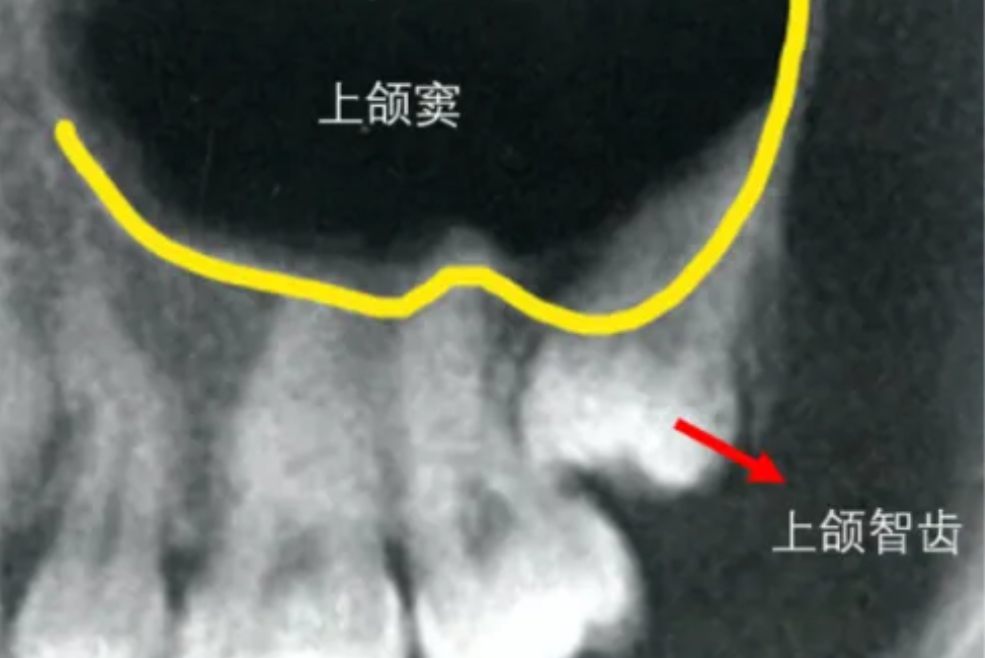

上智齿太靠近上颌窦在拔出智齿的过程中,可能会损伤上颌窦斗底,必要时需要做上颌窦修补手术。

上智齿太靠近上颌窦是否需要拔出,需要结合个人具体情况、牙齿具体生长情况等综合判断。

上颌窦为上颌骨体内的锥形空腔,窦壁为骨质,大部分为薄的密质骨板,内稍有松质骨,最薄的地方只有密质骨。窦壁直接被覆粘膜,支配牙齿及牙周组织的血管、神经,通行于骨内牙槽管之中或粘膜下。